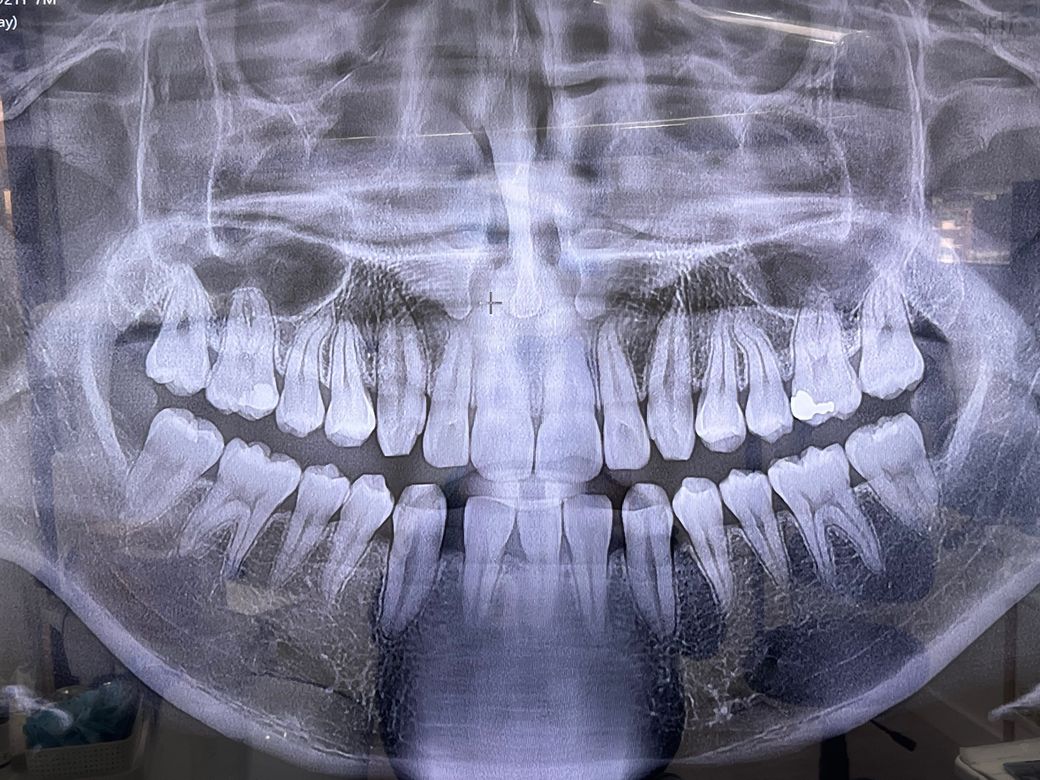

엑스레이 사진상 오른쪽 아래 이빨인데 때운거 떨어졌었다가 4년정도 방치했고 안에 살짝 반투명 회색-연한 반투명 검정 부분 있길래 충치인줄 알고 무조건 갈아낼거라 생각했는데 갈아내지도 않고 바람 몇번 쏘시면서 보시더니 매꿔도 될것같은데 바로 매꿔드릴까요? 하시고 매꿨어요.

충치가 아니였던걸까요? 의사선생님이 잘못보셨다거나 충치를 못봤을 가능성은 없겠죠?

충치 치료 시 모든 검은 부분을 제거하는 건 아닙니다. 감염 상아질까지 다 제거하는 거고, 이환 상아질은 남겨두기도 합니다. 특히 충치가 깊은 특정 부위는 제거했을 때 신경이 노출되면 신경치료 가능성이 있기 때문에 좀 더 조심하는 편이긴 합니다.